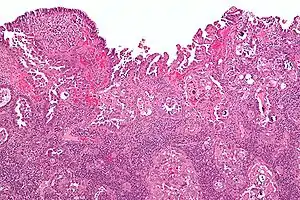

| Micrograph of uterine serous papillary carcinoma. H&E stain. | |

Histopathologically, uterine serous carcinomas is typically characterized by (1) nipple-shaped structures (papillae) with fibrovascular cores (2) marked nuclear atypia (irregularies in the nuclear membrane, enlarged nuclear size), (3) psammoma bodies and (4) cilia.